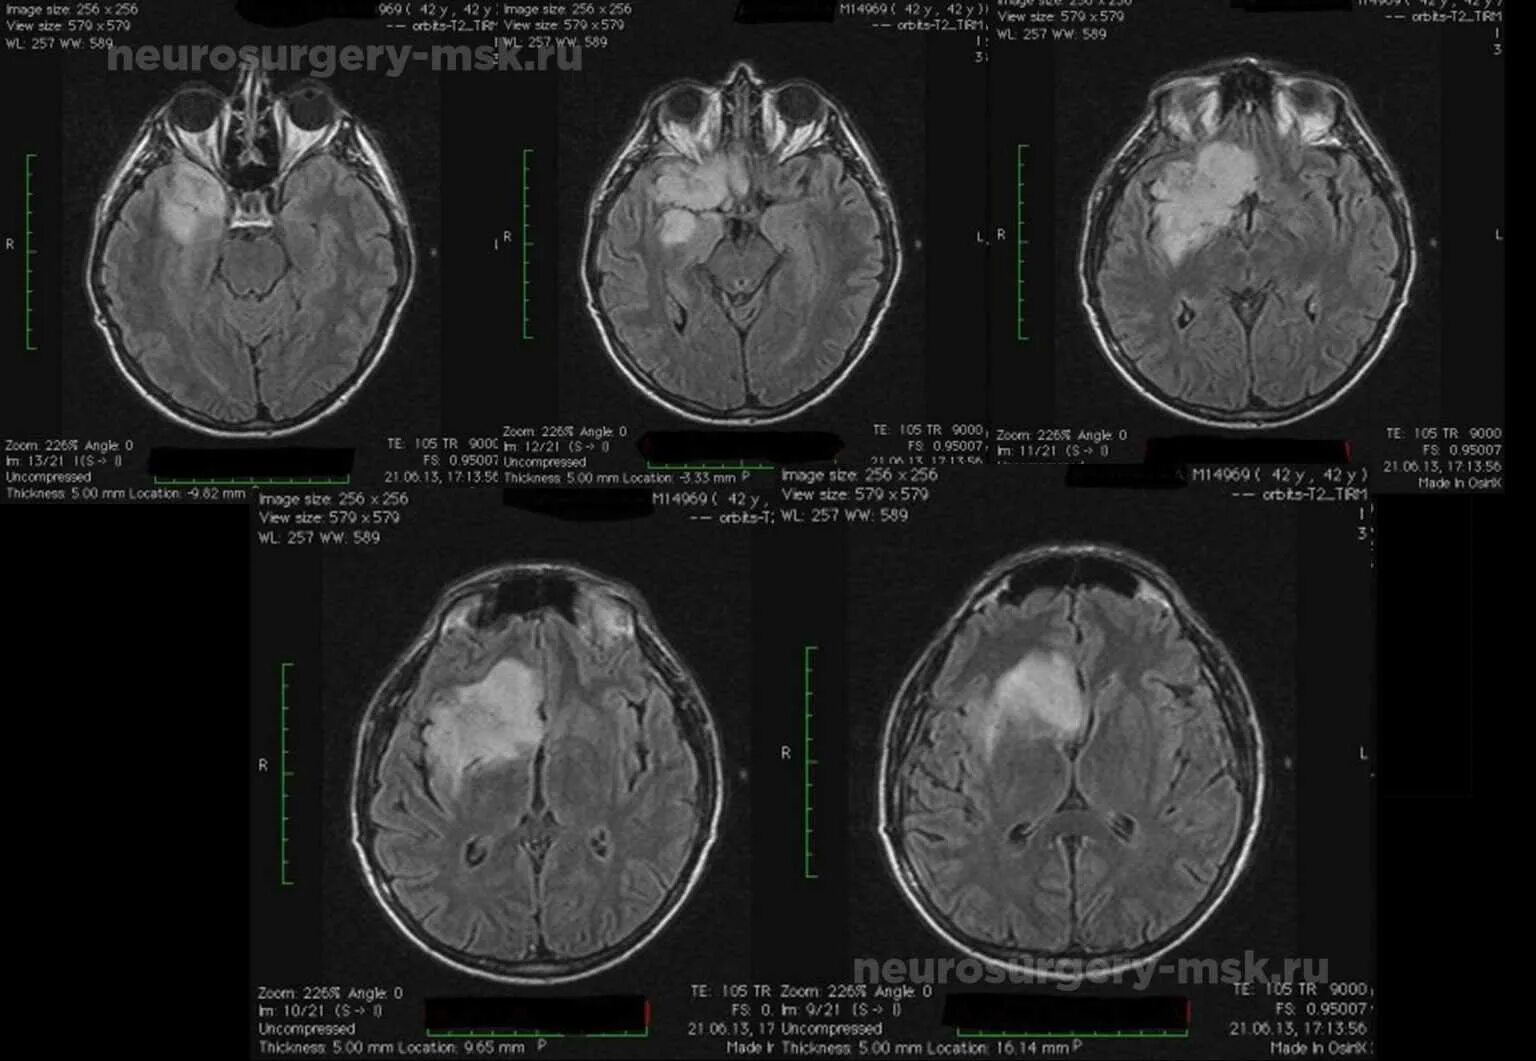

Астроцитома головного мозга прогноз после операции